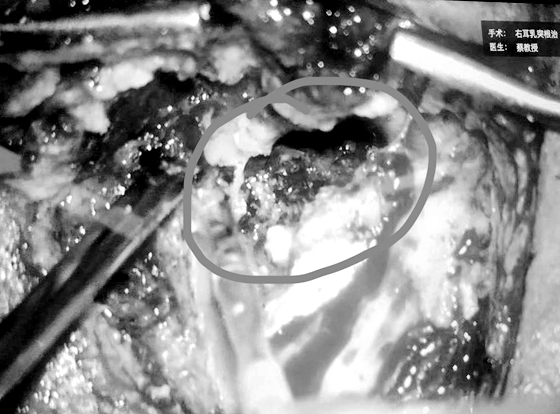

之后,田湘娥教授为其制定了详细的手术计划。次日,在全麻下通过显微镜为其实施了“右乳突根治术”。术中发现:右中耳内见巨大胆脂瘤,乳突骨质及外耳道后壁、上壁骨质破坏,约1.5cm×1cm大小面积硬脑膜裸露,外半规管骨质破坏,可见蓝线,病变鼓膜内陷贴附于鼓室粘膜,听骨链完全消失,咽鼓管鼓口、鼓室内大量胆脂瘤上皮。面神经骨管水平段及垂直均破坏,面神经裸露。在完全没有正常解剖结构作为标志的情况下,耳鼻喉科专家根据术前严密阅片,仅1个半小时,凭借部分已经破坏的残余结构迅速定位并保护好面神经、脑膜等重要结构,彻底清除了胆脂瘤病变及其基膜,充分轮廓化及通畅引流术腔。手术取得成功,术后患者无眩晕、无面瘫症状,次日便下床正常活动。